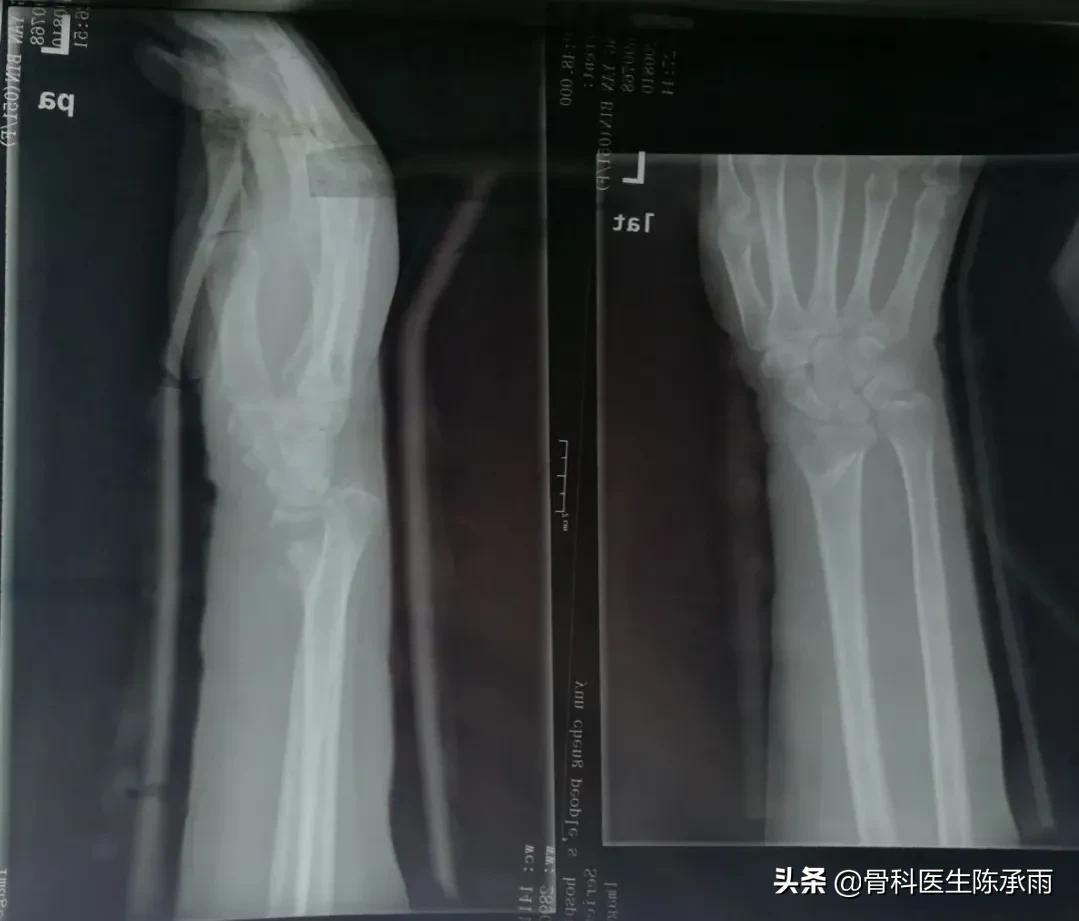

这是我院骨科收治的一名桡骨远端陈旧性骨折女性患者,骨折已经45天,畸形愈合,掌倾角严重缺失,患者心理负担超重。

制定手术方案,术中见骨折愈合稳定,骨质疏松严重,远尺桡关节脱位固定,腕关节旋转受限。

原有骨折关系已不能找到,软组织粘连严重,骨折较疏松,尽量达到功能复位。